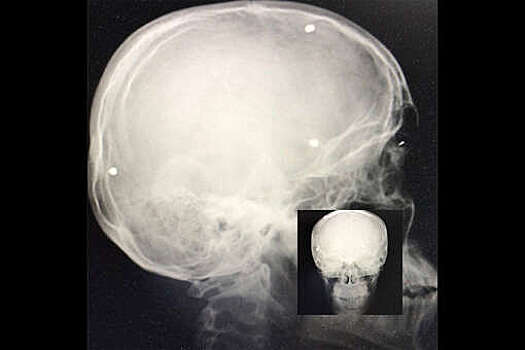

Сургутские врачи шесть часов извлекали охотничью дробь из головы подростка

Врачи Сургутской травматологической больницы спасли 15-летнего подростка с охотничьей дробью в голове. Об этом сообщил директор Депздрава Югры Алексей Добровольский в своем Telegram-канале. В больницу юношу доставила с ранением головы санитарно-авиационная бригада. Медики шесть часов извлекали из головы подростка металлические шарики. Как рассказал Добровольский, один из шариков прошел сквозь весь мозг, чудом миновав жизненно важные центры. После операции пациент пять дней провел в реанимации, затем его перевели в нейрохирургическое отделение. Подросток получил травму 8 августа на реке Северная Сосьва. Местный житель по ошибке попал из ружья в подростка, целясь в гусей, которые находились у реки.